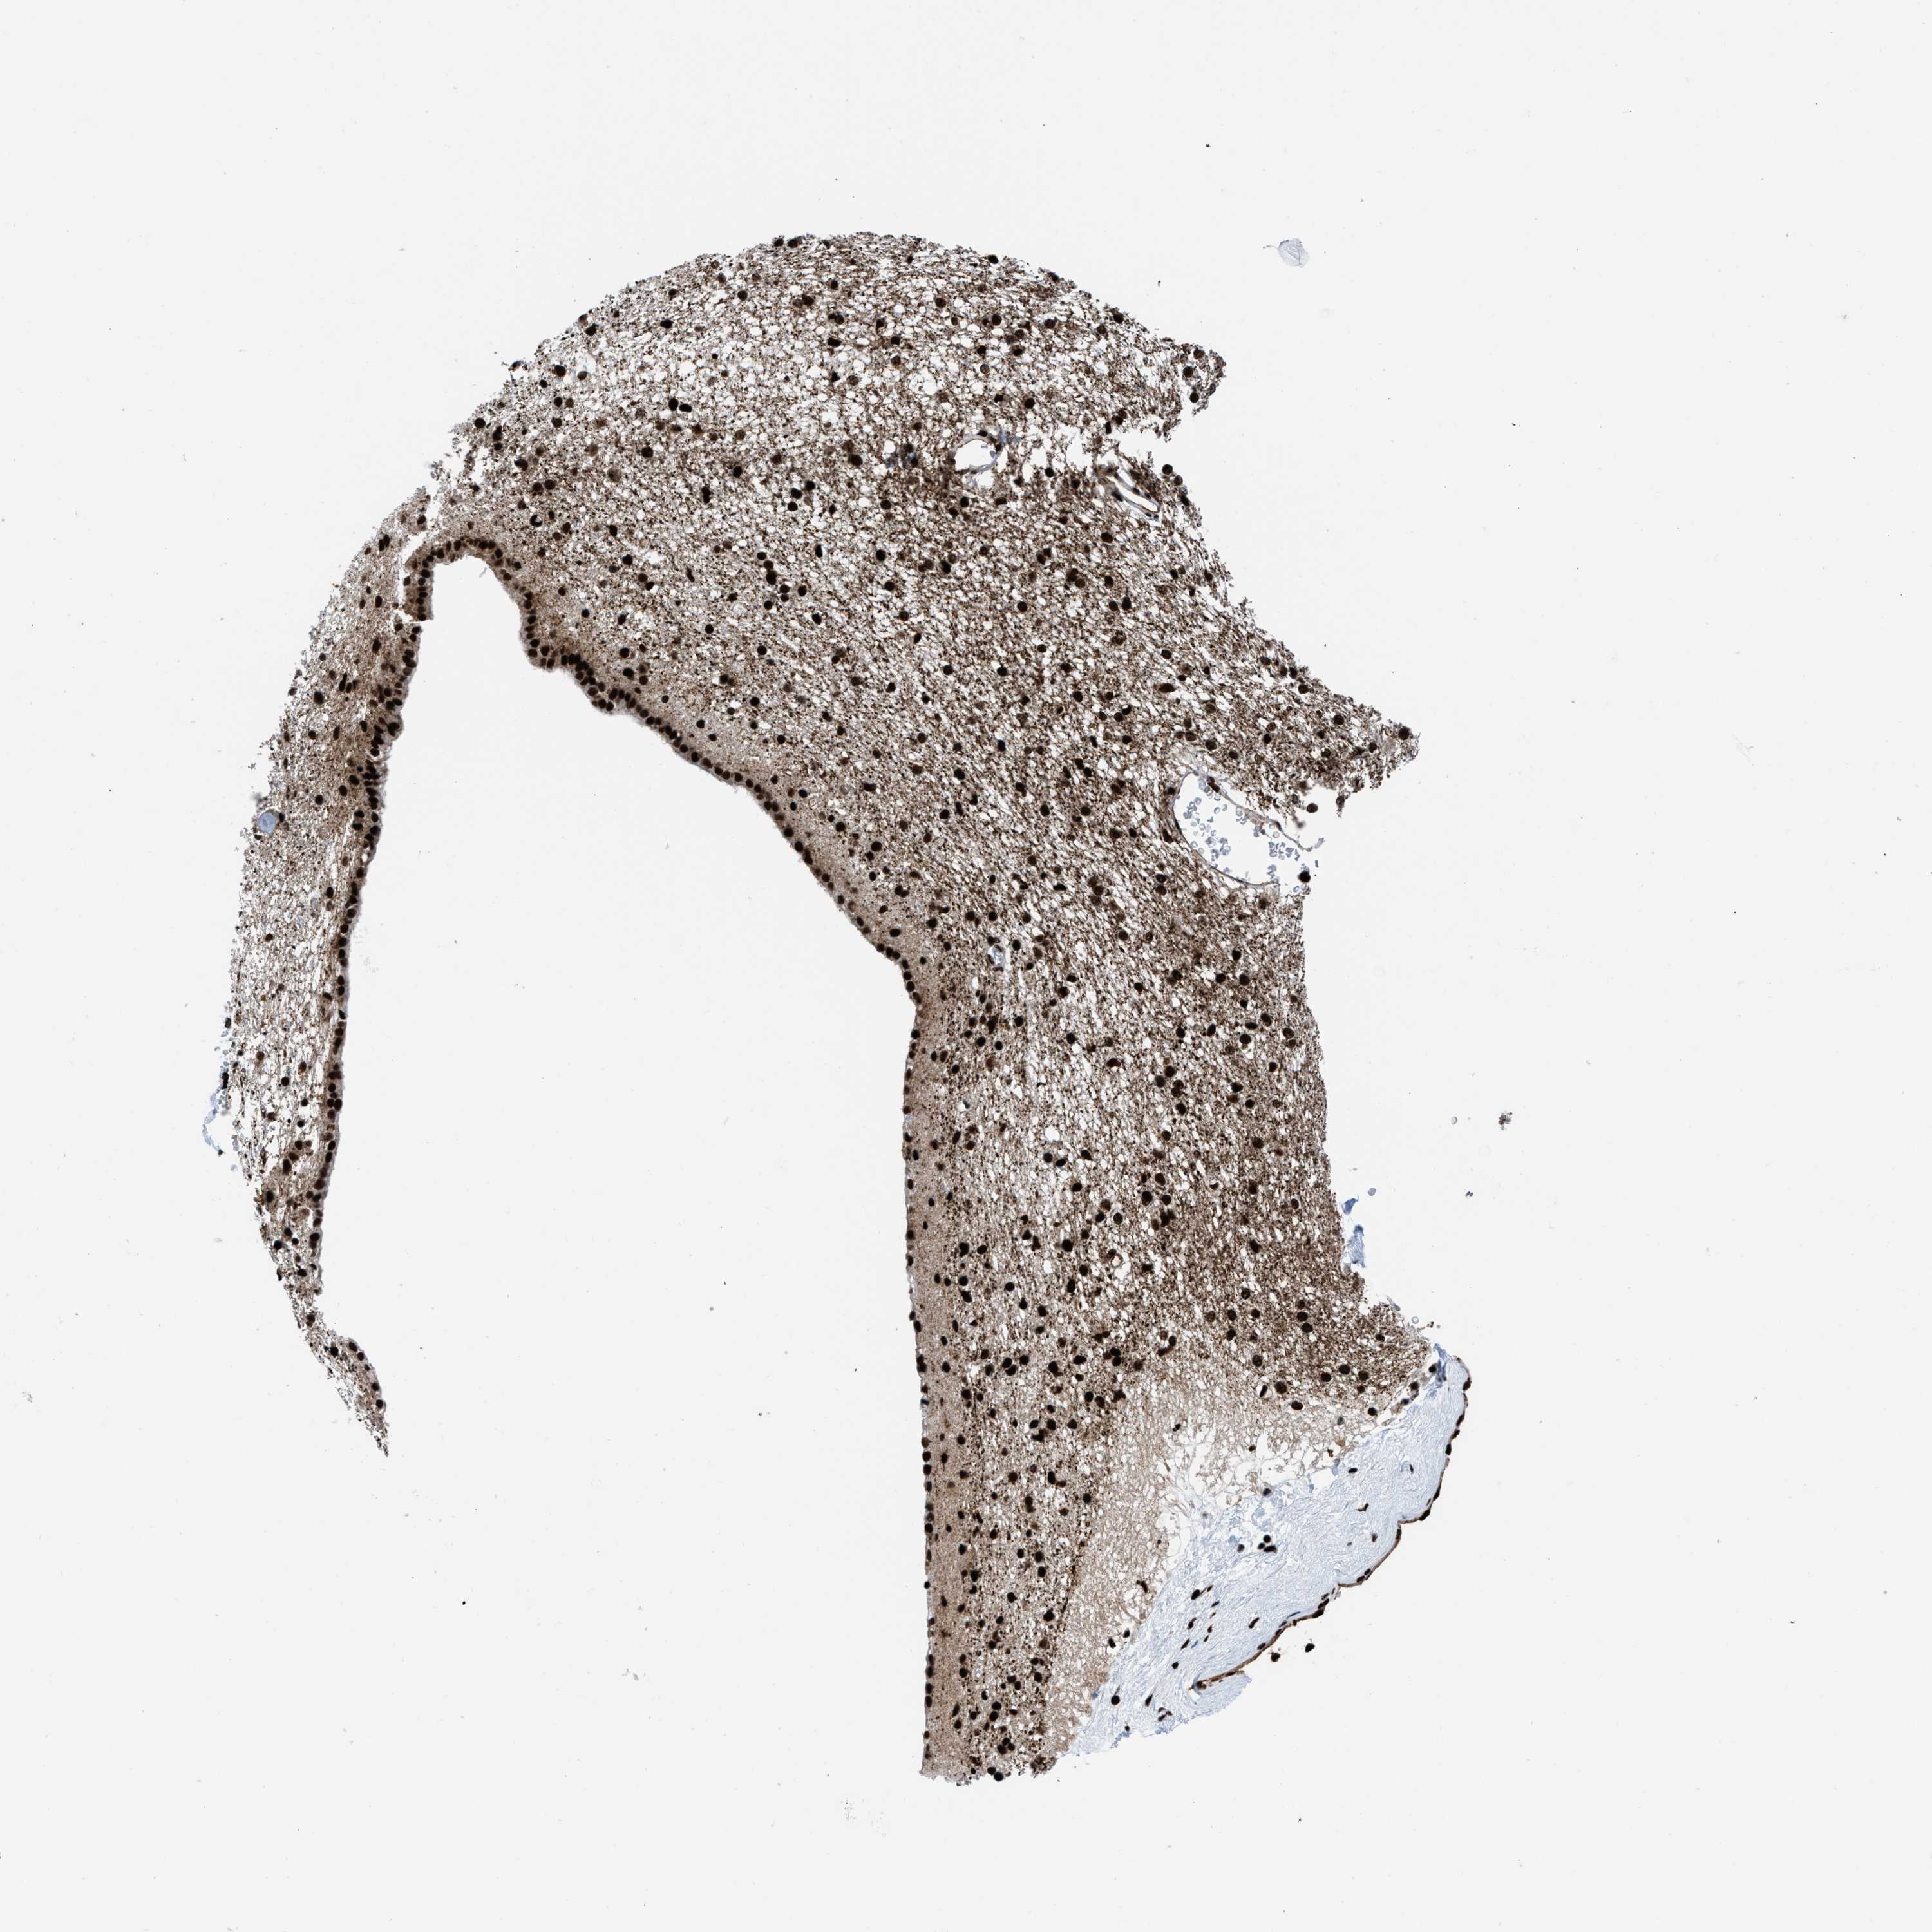

CAUDATE